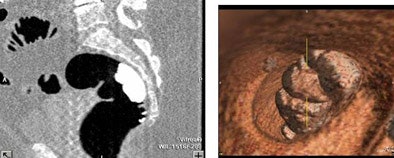

Following automated CO2 insufflation of the colon (PROTOCO2L, E-Z-EM), low-dose abdominal CT was performed on a 16-slice scanner at 50 mAs, 100 kVp, 1-mm collimation, and 0.5-mm reconstruction interval. An attending GI radiologist evaluated the images with primary 2D and 3D problem-solving software, but no computer-aided detection (CAD) or electronic cleansing software.

Compared to optical colonoscopy as the gold standard, however, VC had two false-negative adenomas larger than 10 mm. One was a flat lesion, and none were high-grade dysplasia. Three false-positives were seen in two patients with severe sigmoid diverticulosis due to small untagged fecal balls, recognized for their low density.

"We know that for those patients that had incomplete fecal tagging in the distal part of the colon, pretty much it was all because they ... identified as being constipated," Lu said. "In terms of evaluating these images, we really didn't see any beam-hardening artifact from the barium that compromised the evaluation, to our surprise," he said. Otherwise, fecal tagging was generally adequate.